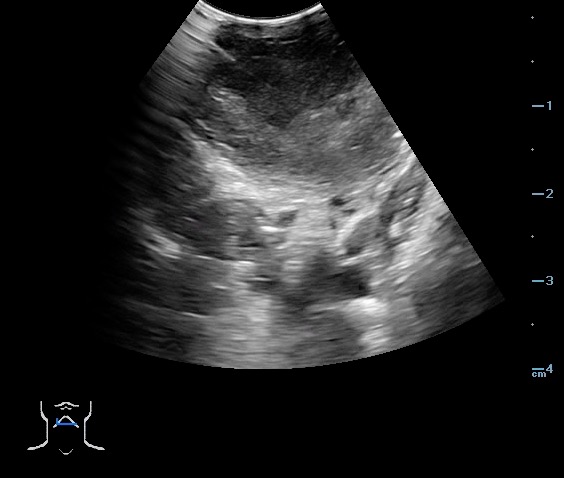

- Peritonsillar abscess is visualized as a hypoechoic or complex cystic structure

- Ultrasound-guided needle aspiration of a PTA:

- The depth of the abscess cavity from the mucosal surface should be noted to determine the length of the needle required to drain the abscess.

- Figure 45. and 46. PTA aspiration

- Figure 49 and 50. PTA Aspiration Resolution